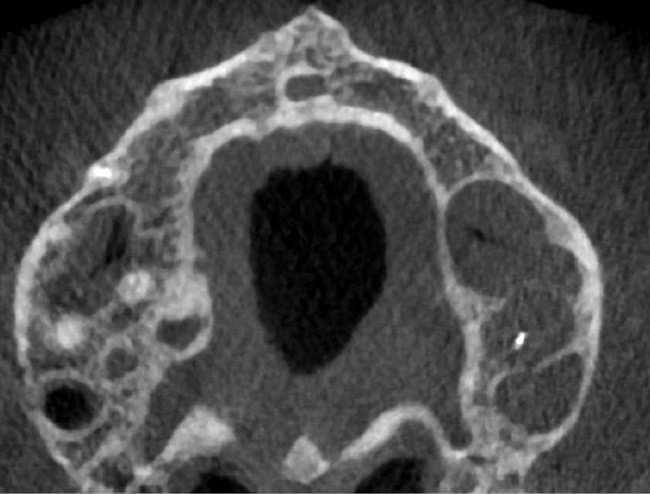

Rebondissant sur l’imagerie 3D et la mise en évidence des anatomies canalaires complexes, Peters, en 2001, décrit l’insuffisance instrumentale dans le traitement endodontique, et montre que 35 % des surfaces sont intactes après préparation canalaire correctement menée [18].

Endal, en 2011, montrait également, en utilisant le micro CT Scanner, l’insuffisance de nettoyage des isthmes inter-canalaires à nos techniques conventionnelles [19]. L’utilisation du laser Er:YAG devenait alors incontournable dans le nettoyage de ces isthmes et des zones non instrumentées (fig. 2 et 3).

Si l’étude de Peters [18] nous montre que l’instrumentation laisse 35 % du volume canalaire non instrumenté, Ricucci et Siqueira montrent que la préparation physico-chimique n’élimine que partiellement les tissus nécrotiques à l’entrée des canaux latéraux, des isthmes et des ramifications apicales, en laissant des tissus enflammés et infectés, en association avec des lésions apicales [29] (fig. 4 et 5).

Fig. 4 – Coupe d’une racine mésiale de molaire mandibulaire avec deux canaux traités. Coupe à 3 mm de l’apex, coloration Brown et Brenn, technique modifiée par Taylor. Ces images montrent un isthme étroit avec une infection bactérienne, ce qui prouve l’importance de désinfecter et d’inclure l’isthme dans les traitements conventionnels et dans les rétropréparations apicales en chirurgie endodontique.